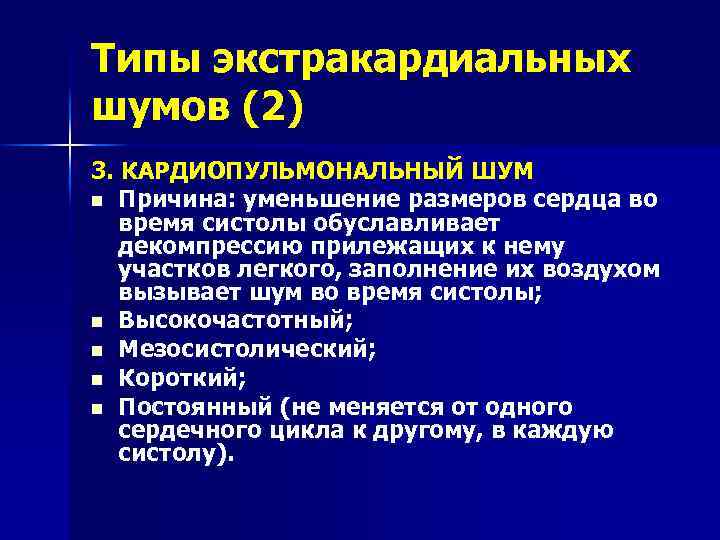

Типы экстракардиальных шумов (2) 3. КАРДИОПУЛЬМОНАЛЬНЫЙ ШУМ n Причина: уменьшение размеров сердца во время систолы обуславливает декомпрессию прилежащих к нему участков легкого, заполнение их воздухом вызывает шум во время систолы; n Высокочастотный; n Мезосистолический; n Короткий; n Постоянный (не меняется от одного сердечного цикла к другому, в каждую систолу).